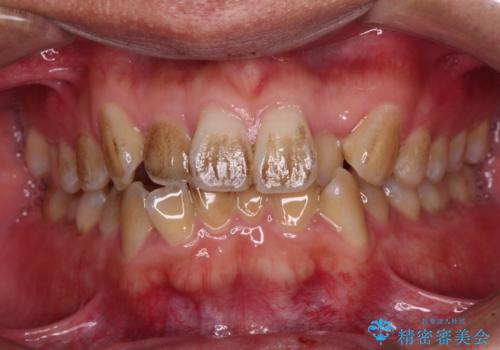

- 前歯のデコボコを気にして来院された患者様です。

極力費用を抑えた上で、自己管理の煩わしの少ない装置を希望とのことで、メタルブラケットによるワイヤー矯正を選択されました。

舌の突出癖があり、デコボコが解消される際に出っ歯傾向になる恐れがあるため、舌のトレーニングを行っていただきながら、矯正治療を進めていくこととしました。